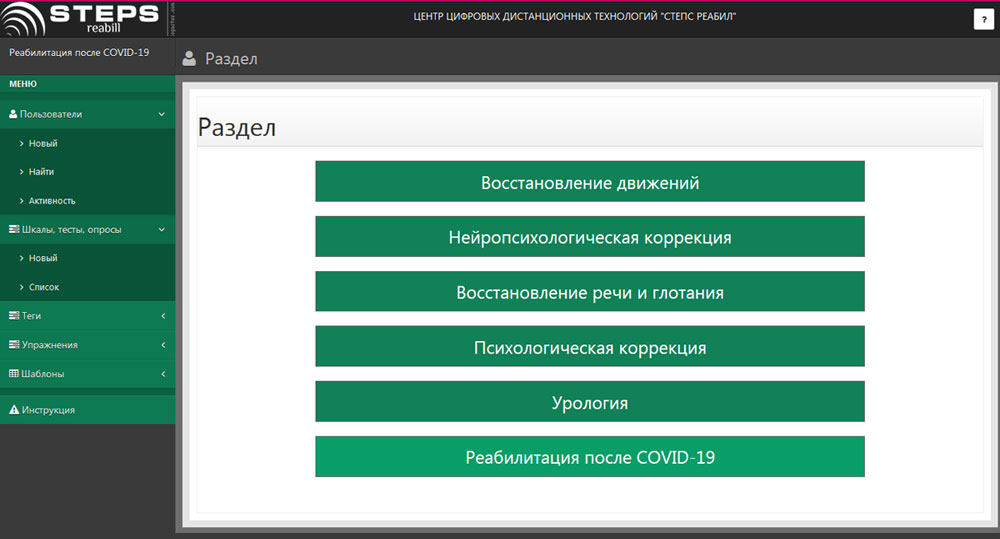

Пироговский Центр и стартап «Виртуальная реабилитация» представили отечественную цифровую платформу для дистанционной реабилитации с применением технологий виртуальной реальности и биологической обратной связи VRmedSoft на VII ежегодной конференции «Цифровая индустрия промышленной России» (ЦИПР-2022) в Нижнем Новгороде.

Компания «Степс Спорт» под научным руководством Генерального директора Пироговского Центра, члена-корреспондента РАН, профессора Олега Карпова стала резидентом инновационного научно-технологического центра «Сириус» с проектом по созданию «Платформы цифровой реабилитации взрослых и детей».

Пироговский Центр открыл свободный доступ к онлайн-платформе реабилитации для медучреждений и органов соцзащиты.

Решение «Степс Реабил» вошло в проект «Лучшие практики борьбы с пандемией».

Внедрены новые возможности телемедицины, в том числе готовые цифровые решения для двигательной, речевой и психологической реабилитации на домашнем этапе лечения, что обеспечивает наибольшую эффективность и непрерывность процесса восстановления наших пациентов